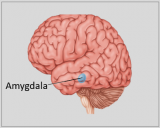

La neuroanatomie est la branche de l'anatomie qui étudie l'anatomie du système nerveux, c'est-à-dire la structure, la fonction et l'organisation du système nerveux.

Le système nerveux est l'un des systèmes les plus complexes du corps humain, et il comprend le cerveau, la moelle épinière, les nerfs périphériques et les ganglions nerveux. La neuroanatomie s'intéresse à la manière dont ces structures sont reliées les unes aux autres, comment les signaux sont transmis entre les cellules nerveuses, et comment les différentes parties du système nerveux travaillent ensemble pour contrôler les fonctions corporelles et cognitives. Les neuroanatomistes utilisent des techniques d'imagerie avancées, comme l'imagerie par résonance magnétique (IRM), la tomographie par émission de positons (TEP) et la microscopie pour visualiser les structures et les fonctions du système nerveux.